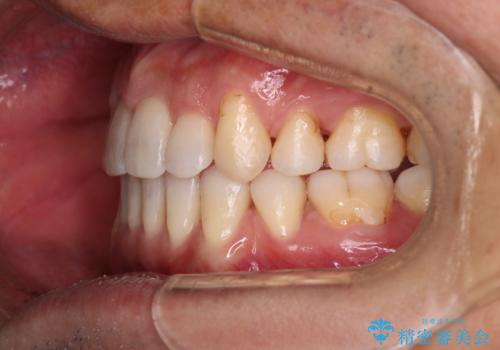

- 治療計画

叢生量が大きいため、上下顎両側4番を抜歯しました。矯正治療による歯肉退縮の著しい悪化もなく、主訴であるガタつきも改善できました。